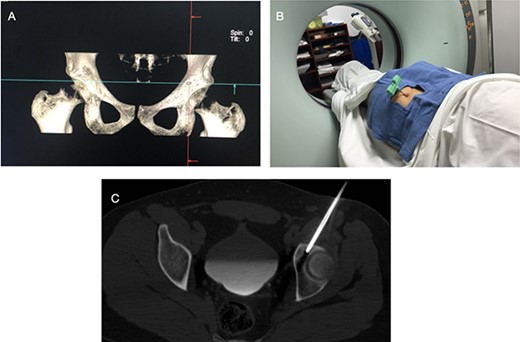

The procedure was made with general anesthesia and in supine position. A 1-cm incision was made for an anterior approach over the hip joint. Careful blunt dissection was done. Percutaneous technique was used with the guidance of a 64 slice Somatom sensation CT scanner (Siemens AG Munich, Germany) with interval cuts of 2 mm to locate the OO. Intravenous contrast was administered to identify the vascular structures at risk (Fig. 3). A 13G × 100 mm bone marrow biopsy needle was used. Image guidance was performed by a senior radiologist (ES). Once the OO was located, accurate insertion of the needle was monitored, and drilling was done manually to help precision in depth (Fig. 4). Multiple bone fragments were obtained and sampled. Immediate image verification showed a space missing the nidus OO. To avoid leaving remnant nidus, curettage was added on the edges and the deep margin of the tumor. Bone samples were sent to histological evaluation and OO diagnosis was confirmed. Wound pain management was administered for 2 weeks and night symptoms disappeared immediately. Complete relief was achieved 3 weeks later. A 12-month follow-up post treatment reported no recurrence of pain and no complications with wound management. ROM and athletic activities are painless. No soft tissue complications were reported.

CT with intravenous contrast showing the femoral vessel (yellow arrow) before the procedure to obtain proper approach (red arrow showing the OO).